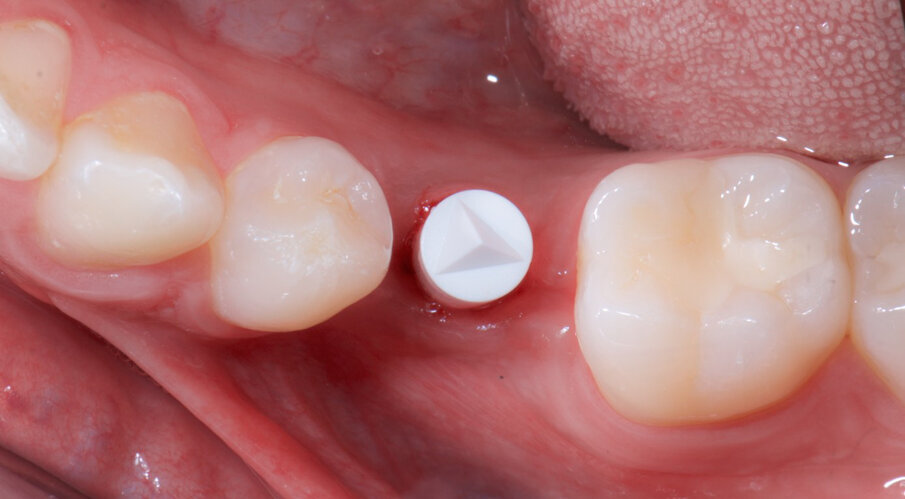

Fig. 13_Lo strato inferiore abutment serrato in posizione realizzato in Enamic IS.

Fig. 14_La qualità dei tessuti del tragitto transmucoso grazie alla rilocazione del margine del pilastro implantare Dentsply Sirona Ankylos.